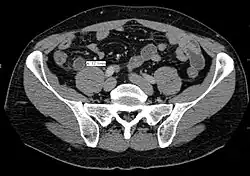

Computed tomography

Where it is readily available, computed tomography (CT) has become frequently used, especially in people whose diagnosis is not obvious on history and physical examination. Although some concerns about interpretation are identified, a 2019 Cochrane review found that the sensitivity and specificity of CT for the diagnosis of acute appendicitis in adults was high.[63] Concerns about radiation tend to limit use of CT in pregnant women and in children, especially with the increasingly widespread usage of MRI.[64][65]

The accurate diagnosis of appendicitis is multi-tiered, with the size of the appendix having the strongest positive predictive value, while indirect features can either increase or decrease sensitivity and specificity. A size of over 6 mm is both 95% sensitive and specific for appendicitis.[66]

However, because the appendix can be filled with fecal material, causing intraluminal distention, this criterion has shown limited utility in more recent meta-analyses.[67] This is as opposed to ultrasound, in which the wall of the appendix can be more easily distinguished from intraluminal feces. In such scenarios, ancillary features such as increased wall enhancement as compared to adjacent bowel and inflammation of the surrounding fat, or fat stranding, can be supportive of the diagnosis. However, their absence does not preclude it. In severe cases with perforation, an adjacent phlegmon or abscess can be seen. Dense fluid layering in the pelvis can also result, related to either pus or enteric spillage. When patients are thin or younger, the relative absence of fat can make the appendix and surrounding fat stranding difficult to see.[67]